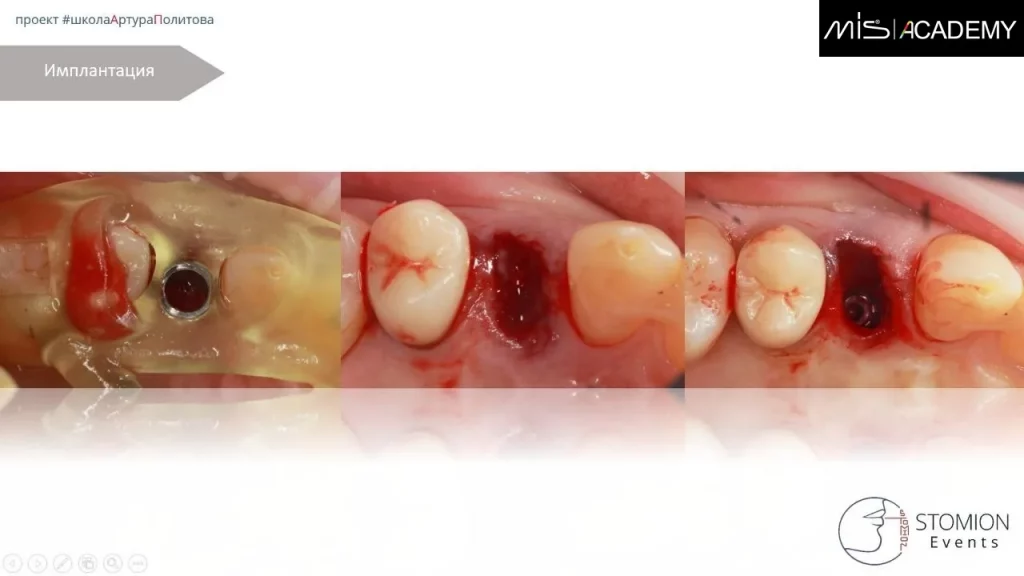

- Удаление 1.4.

- Формирование гомогенного кровяного сгустка.

- Одномоментная имплантация в нёбный корень MIS C1 3,75×11,5.

- СТТ с бугра вестибулярно.

- Коннект абатмент, индивидуальный ФДМ для создание клапана и первичного заживления.

- Швы, БФ-6.

Параллельно установлен имплантат MIS C1 5×8 в позиции 2.7.